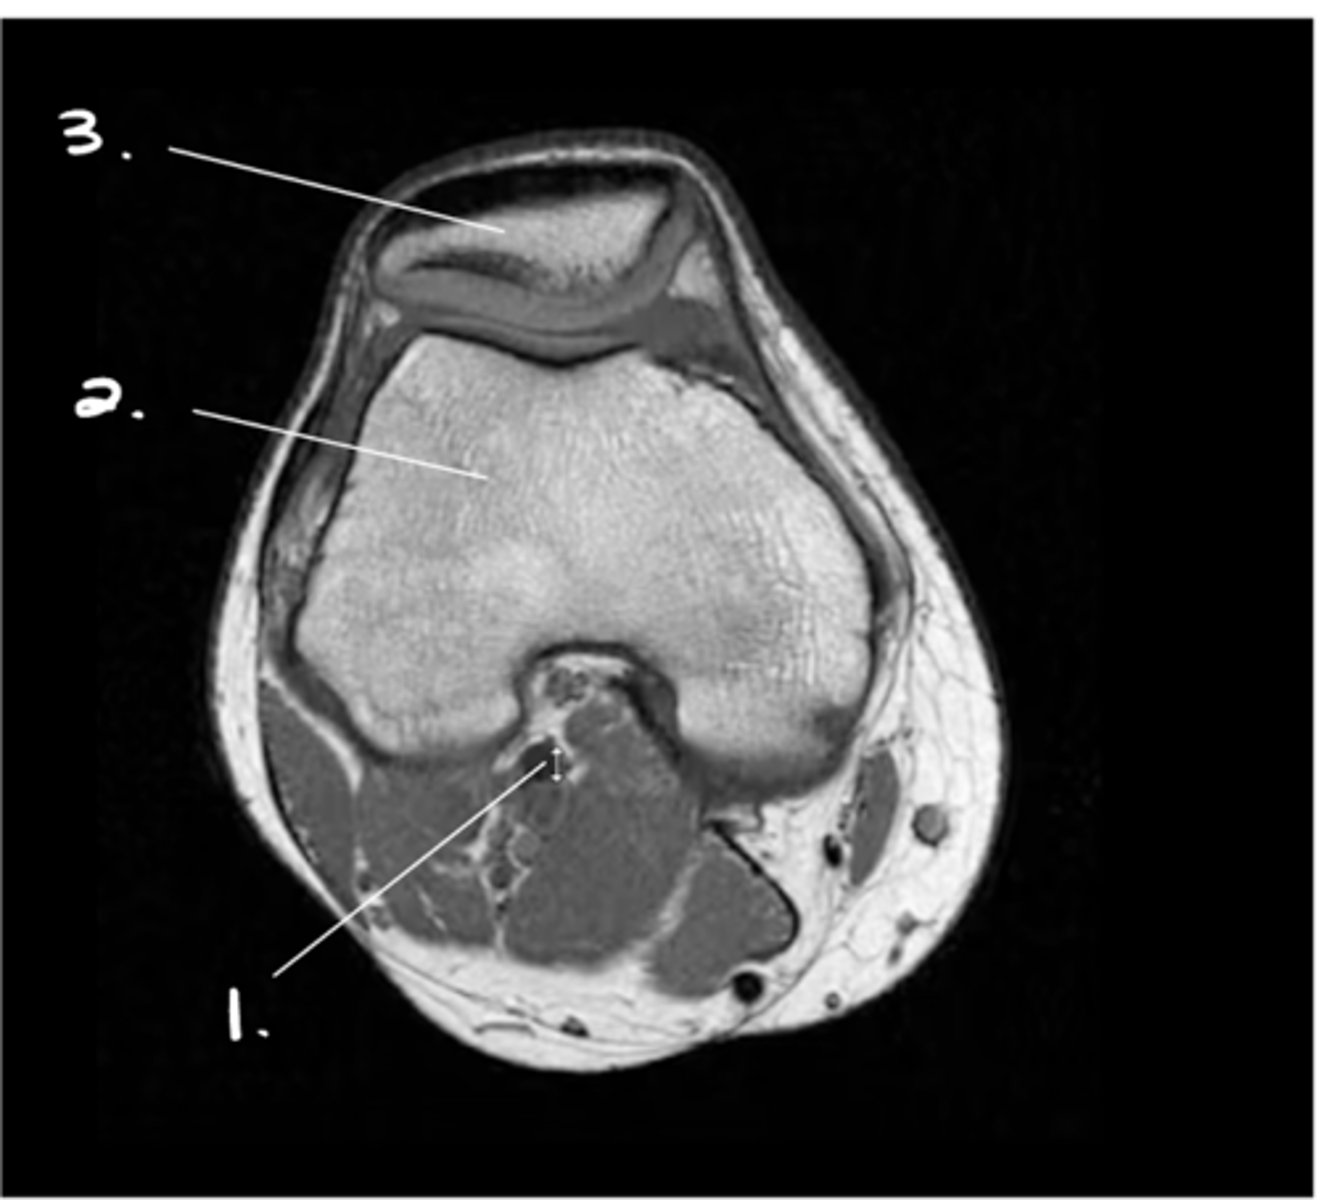

1. Hyaline cartilage (all of the grey)

2. Meniscus (looks kind of like a thickening of the cartilage from this angle)

Label 1 & 2.

Label 1-3.

Medial meniscus

Label this structure.